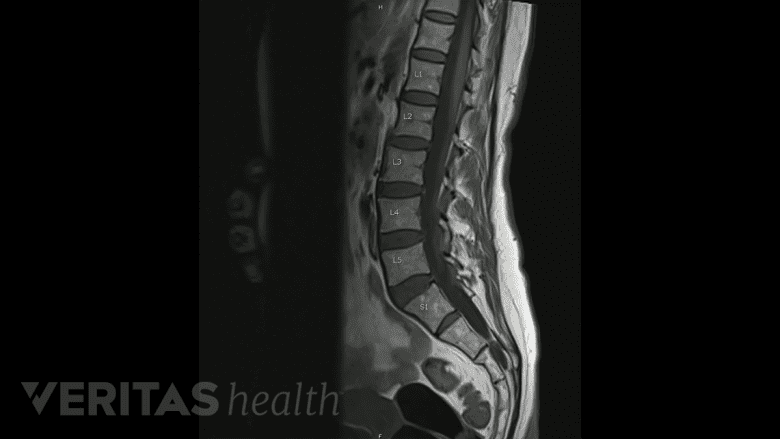

MRI scans are used to create 3D images of the spine before a robotic surgical procedure.

In the planning stage, the surgeon first creates a 3D model of the patient's spine using computed tomography (CT) scans or magnetic resonance imaging (MRI) scans. The surgeon then uploads this 3D model into the robotic system. The robot assesses the model to reconstruct the surgical field and independently registers each component of the patient’s spine.